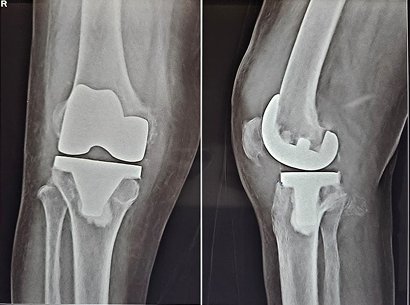

Revision knee and hip replacement surgeries are specialized procedures aimed at correcting issues from previous joint replacements. Dr. Nevil K. Gajera provides advanced care to restore mobility, reduce pain, and improve quality of life for patients facing complications or wear from earlier surgeries.

Each surgery is carefully planned using advanced imaging and precision surgical techniques. Whether addressing loosening, infection, joint instability, or implant failure, the procedures are tailored to the patient’s unique needs.

Dr. Gajera specializes in techniques such as revision total knee replacement, revision hip arthroplasty, and complex joint reconstruction—helping patients regain strength, function, and a pain-free lifestyle.

Knee Revision Surgery Ahmedabad